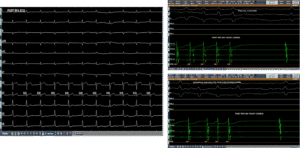

As seen in the baseline ECG and intracardiac electrograms (Page 3 of the case file), the patient demonstrated narrow complex tachycardia with organized atrial activity. Intracardiac recordings showed consistent atrial activation patterns suggestive of a re-entrant arrhythmia rather than focal atrial tachycardia.

During the electrophysiology study (Page 4), tachycardia was induced using programmed stimulation.

Ventricular entrainment pacing demonstrated a VAAV response, confirming an atrial tachycardia/atrial flutter mechanism. The tachycardia cycle length (TCL) was approximately 310 ms.

Since atrial flutter typically represents a macro re-entrant circuit, mapping of both right atrium (RA) and left atrium (LA) was planned using a high-density grid catheter to create a Local Activation Time (LAT) map.